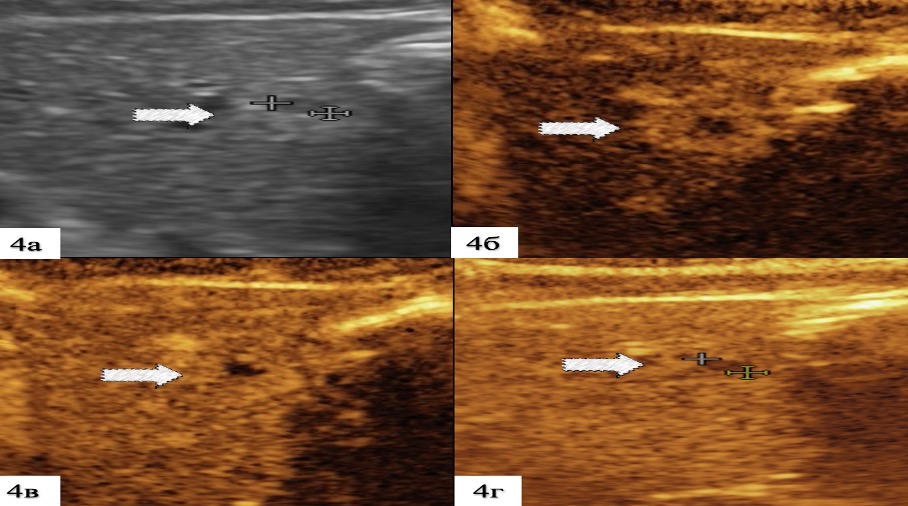

4. Рисунок 4. Мультипараметрическая УЗ картина метастаза КРР в печень | |

| Тема | ||

| Тип | Результаты исследования | |